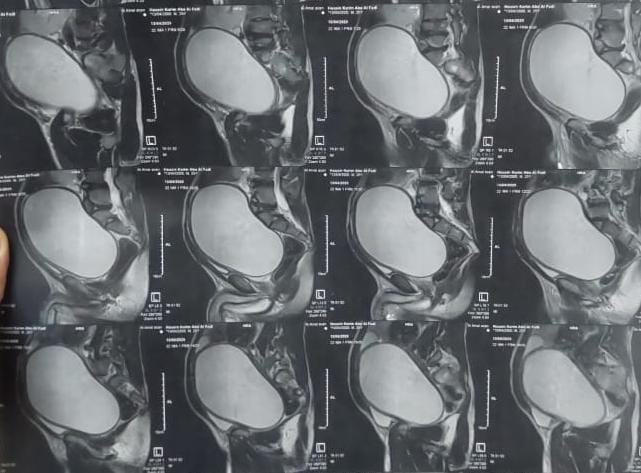

كان مستشفى جراحة المسالك قد استقبل مريضا، ٢٦ عاما، يعاني من كيس كبير يقع بين المثانة والمستقيم بأبعاد تصل إلى 12×14×18 سم، وممتد إلى منطقة البطن، وكان مصدر هذا الكيس الحويصلة المنوية، وقد تسبب ذلك في إصابته بإلتهابات متكررة، واحتباس للسائل المنوي،

بالإضافة إلى وجود عيب خلقي في الحالب الأيمن، حيث كان يفتح في كيس الحويصلة المنوية، ليتمكن الفريق الطبي من استئصال الكيس بعد فصله بعناية فائقة عن الالتصاقات الشديدة التي كانت تربطه بالأمعاء، كما قام الفريق بإعادة زرع الحالب الأيمن في المثانة البولية بفتحة جديدة، لتستقر حالة المريض بعد ذلك.